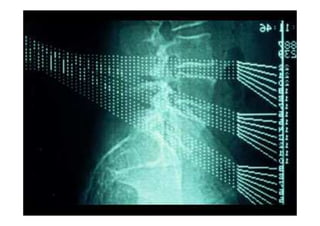

• Em todos os casos de escoliose estrutural, é essencial a investigação

apropriada, a medida radiográfica das curvas e a observação cuidadosa.

Escoliose

Apresentação de Casos Clínicos

• Escoliose Idiopática do Adolescente

• Resumo do caso: Escoliose idiopática do adolescente tratada

cirurgicamente com artrodese da coluna T4L1 com parafusos

pediculares.

• Paciente (dados): feminino, 13+2 anos, Risser 3, menarca há

9 meses.

• História: Deformidade da coluna percebida pela mãe há 3

meses. Nega tratamento prévio. Nega demais doenças ou uso

de medicações.

• Diagnóstico(s): Escoliose idiopática do adolescente, Lenke

1B-. Tratamento(s): Artrodese da coluna por via posterior T4-

L1 com parafusos pediculares.

• Seguimento ("Follow up"): Seguimento de 2

anos. Literatura:

• Resultado Final: Artrodese seletiva torácica T4-L1, obtida

compensação do tronco e nivelação dos ombros.

Fonte: Portal da SBC – casos clínicos

Rx ortostático AP - Pré-

operatório